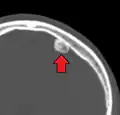

Osteoma of external auditory meatus

An osteoma (plural osteomas or less commonly osteomata) is a new piece of bone usually growing as a benign tumour on another piece of bone, typically the skull. When grown on other bone it is known as "homoplastic osteoma"; on other tissue it is called "heteroplastic osteoma".[1]